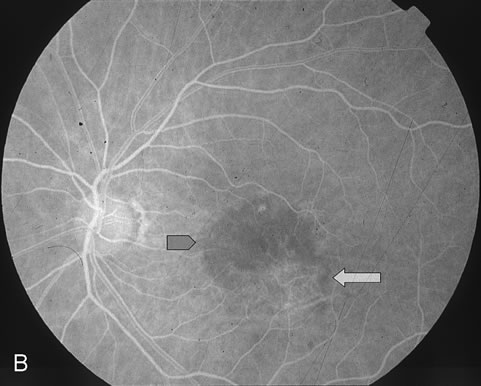

The ideal light energy dose, or fluence, to safely treat CNV was modeled on primate and early-phase studies that varied the parameters of laser irradiance, fluence, and treatment duration.8 Preliminary clinical studies demonstrated untoward effects of retinal vascular closure when a light energy dose of 150 J/cm2 was administered.20 This led to the recommendation in the phase III prospective clinical trials for PDT treatment at 50 J/cm2. Repetition of PDT treatment every 12 weeks was allowed if recurrent CNV leakage was present on fluorescein angiography and examination.21–23 The irradiance of 600 mW/cm2 used for PDT is markedly less than that used for thermal laser photocoagulation (which is typically in the range of 100 to 1000 W/cm2).8 Figures 1D and E demonstrate the typical CNV hypoperfusion on fluorescein angiogram noted at 4 weeks status-post PDT with verteporfin for predominantly classic CNV in AMD (Fig. 1A to C).

Fig. 1. A. Color fundus photograph of subfoveal CNV in a patient with AMD as well as myopia. B. Early-phase FA (35 seconds) demonstrates predominantly classic subfoveal CNV (as defined by the TAP study).23 C. Late-phase FA (3:20) demonstrates hyperfluorescent leakage from subfoveal CNV. D. Early-phase FA (42 seconds) at day 7 status post verteporfin-PDT demonstrates the typical ring of hypofluorescence corresponding to the treated area. E. Late phase FA (3:01) at day 7 status post verteporfin-PDT demonstrates a small, central area of fluorescein staining.